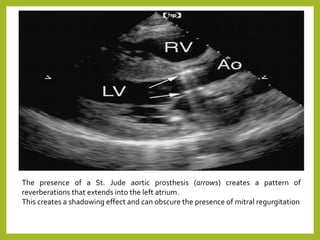

The presence of a St. Jude aortic prosthesis (arrows) creates a pattern of

reverberations that extends into the left atrium.

This creates a shadowing effect and can obscure the presence of mitral regurgitation